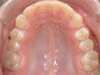

Avant

Après